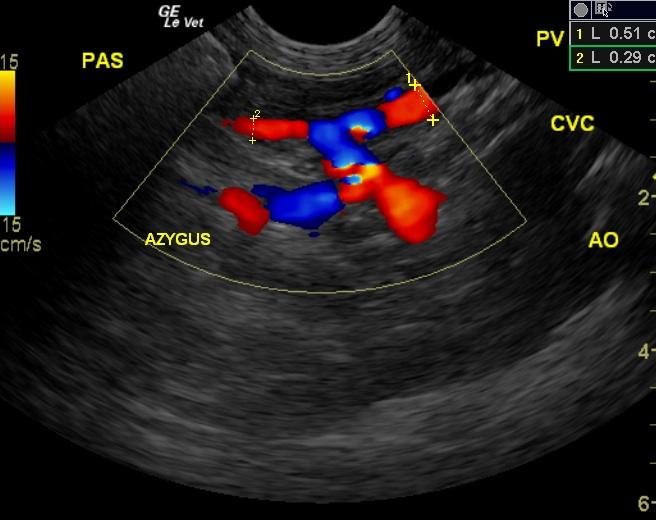

A 4-year-old F Yorkshire Terrier dog was presented at an emergency facility for acute onset disorientation, unresponsiveness, and vomiting. On physical examination, she appeared blind and was disoriented. Abnormalities on CBC and blood chemistry were low MCV and hypocholesterolemia. The patient was treated with K/D diet. Recheck blood work a month later showed alkaline phosphatase normalized and a normal WBC. Eight months later, the owner reported that the patient was still vomiting 1-2 times a week and getting Lactulose. CBC showed low MCV and MCHC.

A 4-year-old F Yorkshire Terrier dog was presented at an emergency facility for acute onset disorientation, unresponsiveness, and vomiting. On physical examination, she appeared blind and was disoriented. Abnormalities on CBC and blood chemistry were low MCV and hypocholesterolemia. The patient was treated with K/D diet. Recheck blood work a month later showed alkaline phosphatase normalized and a normal WBC. Eight months later, the owner reported that the patient was still vomiting 1-2 times a week and getting Lactulose. CBC showed low MCV and MCHC. The only change on blood chemistry was elevated ALP activity. Nutrical was added to the therapy. Two weeks later, the patient was presented for vomiting. On physical examination, the patient was febrile and slightly disoriented. The patient was treated with metronidazole and L/D diet. The following morning the owner reported that the patient was back to normal.